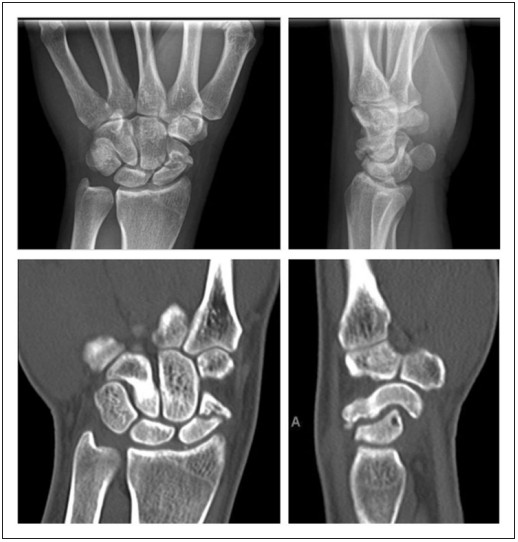

The image displays pre-op X-rays/CTs of scaphoid waist nonunion, with 10mm erosion/bone loss, humpback deformity, and early wrist instability.Fig.1 Pre-operative radiographs (above) and computed tomographic scans (below) showing scaphoid waist nonunion, with approximately 10 mm of cystic erosion and bone loss at the nonunion site, with humpback deformity of the scaphoid and an early dorsal intercalated segment instability deformity of the wrist. (Dodds S. D., et al., 2018)